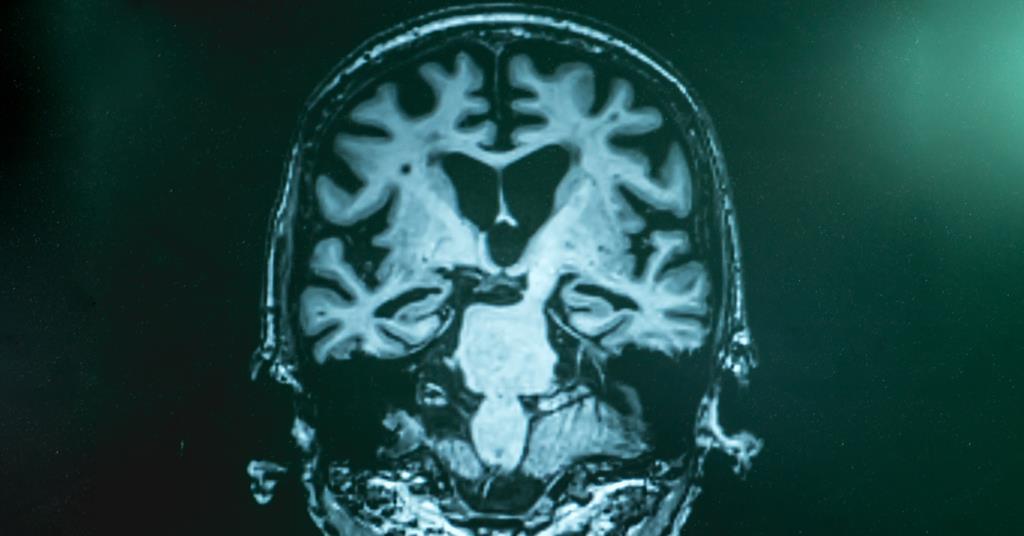

Chronic wasting disease (CWD), a fatal prion disease affecting deer and other cervids, is spreading across North America, raising concerns about potential human transmission. The disease, which causes severe neurological decline, is difficult to detect and has no cure. Researchers are intensifying efforts to understand and control CWD, with some studies suggesting prions could eventually infect humans. The disease's spread is exacerbated by animal feeding operations and environmental persistence of prions, posing significant ecological and public health challenges.

Mad cow disease, caused by prions, emerged in the 1980s, leading to a ban on British meat imports and the culling of millions of cattle. The disease, which can be transmitted to humans through contaminated meat, resulted in variant Creutzfeldt-Jakob disease (vCJD) and raised concerns about potential future cases. While the outbreak changed meat industry practices and led to blood donation restrictions, only a small number of vCJD cases have been reported. Prions also pose a threat in other animals, such as chronic wasting disease in deer, with potential implications for public health.

Scientists are concerned about the spread of chronic wasting disease, also known as "zombie deer disease," and fear it may mutate to infect humans. The disease, which is 100% fatal and has no treatments or vaccines, has been reported in deer, elk, and moose in multiple countries. While the most likely route of transmission to humans would be through consuming infected venison, there are worries that the disease could evolve to spread to humans. Research has shown that the disease may be contagious and could potentially transmit from person to person, raising concerns about the lack of contingency plans and preparedness for a potential spillover into human populations.

Chronic wasting disease (CWD), also known as "zombie deer disease," is spreading among deer populations in North America, raising concerns about its potential to jump to humans. The disease is caused by prions, which are notoriously resilient and can persist in the environment for years. While there is no conclusive evidence of direct transmission to humans, concerns persist due to potential exposure through hunting and consumption of infected animals. The spread of CWD also poses significant ecological and economic risks, threatening deer populations and potentially disrupting ecosystems. International cooperation and comprehensive measures are needed to monitor and control the disease, protect wildlife, and mitigate potential human health implications.

Scientists are concerned that Chronic Wasting Disease, also known as 'zombie deer disease,' which is nearly 100% fatal to animals, may be evolving to infect humans. The disease, caused by misfolded proteins called prions, is spreading rapidly in deer populations across the US and parts of Canada. There are fears that humans could contract the disease from eating infected venison or through contact with contaminated soil and water. With no treatments or vaccines available, researchers are preparing for a potential outbreak and studying the possibility of the disease passing to humans or domestic animals.

Chronic Wasting Disease (CWD), also known as "zombie deer disease", is spreading among deer populations in North America, with concerns about its potential to jump to humans. The disease is caused by prions, which are notoriously resilient and can persist in the environment for years. While there is no conclusive evidence of direct transmission to humans, concerns persist due to potential exposure through hunting and consumption of infected animals. The spread of CWD poses significant ecological and economic risks, threatening deer populations, food security, and ecosystem dynamics. International cooperation and comprehensive measures, including surveillance, biosecurity, and research, are needed to address the challenges posed by CWD and protect both wildlife and human populations.

Chronic Wasting Disease, a fatal brain infection affecting deer and other cervids, has been detected in British Columbia for the first time, raising concerns about its spread and potential impact on wildlife populations. The disease, caused by prions, is highly contagious and always fatal with no known treatment or vaccine. While research suggests it's unlikely to jump to humans, the possibility is unsettling. Infected animals can appear healthy, and the disease's prevalence in the environment poses challenges for containment. Efforts to control the disease's spread have so far been unsuccessful, prompting calls for increased surveillance and testing of deer and elk in affected areas.

Scientists suggest that misfolded proteins, similar to prions, could potentially make dementia transmissible under rare circumstances involving medical procedures. Studies have shown that the sticky clumps of amyloid beta protein found in the brains of Alzheimer's patients may behave like prions and spread to other individuals. Concerns have been raised about the potential transmission of Alzheimer's proteins during neurosurgery or tissue transplants. While the evidence is not yet conclusive, better sterilization techniques may be needed for surgical tools to prevent the transmission of misfolded proteins associated with dementia.

Yellowstone National Park has confirmed its first case of "zombie deer disease," formally known as chronic wasting disease (CWD). The illness, caused by prions, gradually shuts down the deer's body, leading to weight loss, stumbling, and loss of energy. CWD has been reported in 31 states across the US and has no treatment or vaccine. While there have been no reported cases of humans contracting the disease, the CDC advises caution for hunters and individuals in contact with deer or elk, recommending protective clothing, avoiding sick animals, and testing meat for CWD before consumption.

A study from the University of Wisconsin-Madison suggests that ticks may play a role in spreading chronic wasting disease (CWD) among deer in Wisconsin. The research found that ticks can harbor and transmit the prion responsible for CWD, potentially infecting other animals. The study also highlights the importance of land stewardship in managing tick populations and suggests that ticks could be used as a screening tool for CWD in deer populations. However, further research is needed to determine if prion-carrying ticks actually cause transmission to other deer.